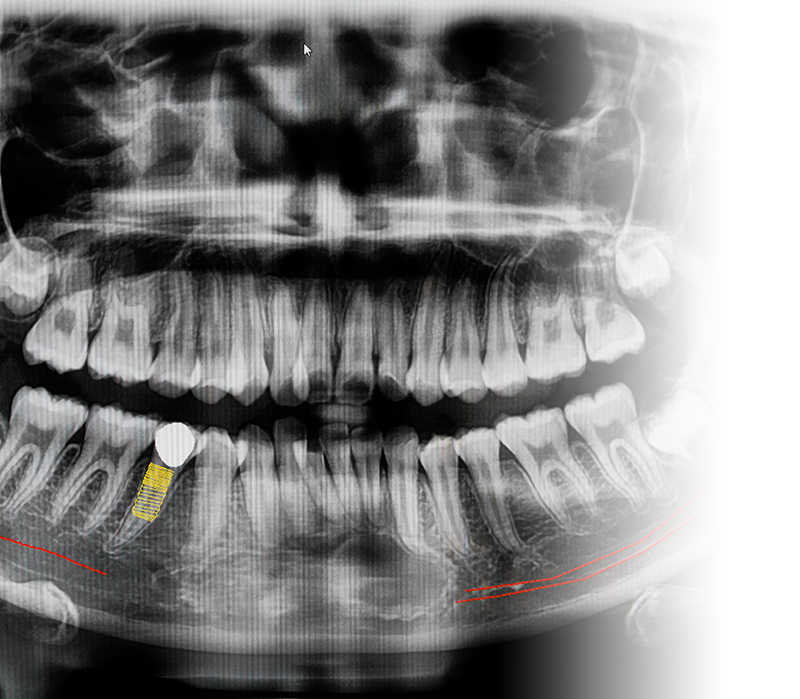

要進行植牙的民眾,一定會聽到關於人工牙根的相關問題,例如:人工牙根材料是什麼、人工牙根費用要多少等問題。相信點進來看這篇文章的民眾們都是第一次接觸到植牙相關的問題,因為這中間涉及到不少專業的醫療知識,雖然網路上的相關資訊很多,但是要自行一一查閱對民眾來說也需要耗費不少時間,若此時能提供經過統整的資料相信能幫助到民眾不少,台北顯微根管推薦- 來德牙醫診所這裡將會對統整關於人工牙根、人工牙根材料、人工牙根費用的相關問題。

人工植牙要多久這問題,是有眾多因素同時影響的。最直接的因素便是患者本身的口腔狀況,如果在人工植牙前的牙周狀況就非常不佳,同時有許多牙周問題需要解決,則光是前期治療牙周就需要花費許多時間。或是將植體植入齒槽骨後,齒槽骨與植體的癒合情況不佳,也會拉長植牙要多久的時間,因此詳細關於植牙要多久的時間,還須與醫生討論作個案分析。

精明的消費者追求高CP值植牙費用是人之常情,但套用在醫療上卻要相當謹慎。來德牙醫診所周承澤醫師指出,植牙屬於客製化的療程,每位患者口腔狀況不同,有些人需要補骨補肉,有些人下顎齒槽骨神經分布特殊,植牙特別講究精準細膩手法,有些人上顎骨過薄,每位患者療程需求差異性極大。

做任何事都有風險以及後遺症,絕對少不了植牙後遺症和風險,植牙是一項精密複雜的手術,面對口腔結構組織各異的病患,如何製訂嚴謹周全的植牙計畫,避免植牙失敗後遺症,相當考驗植牙醫師功力,再強的牙醫師都還是會遇到患者植牙有後遺症嗎的困惑。